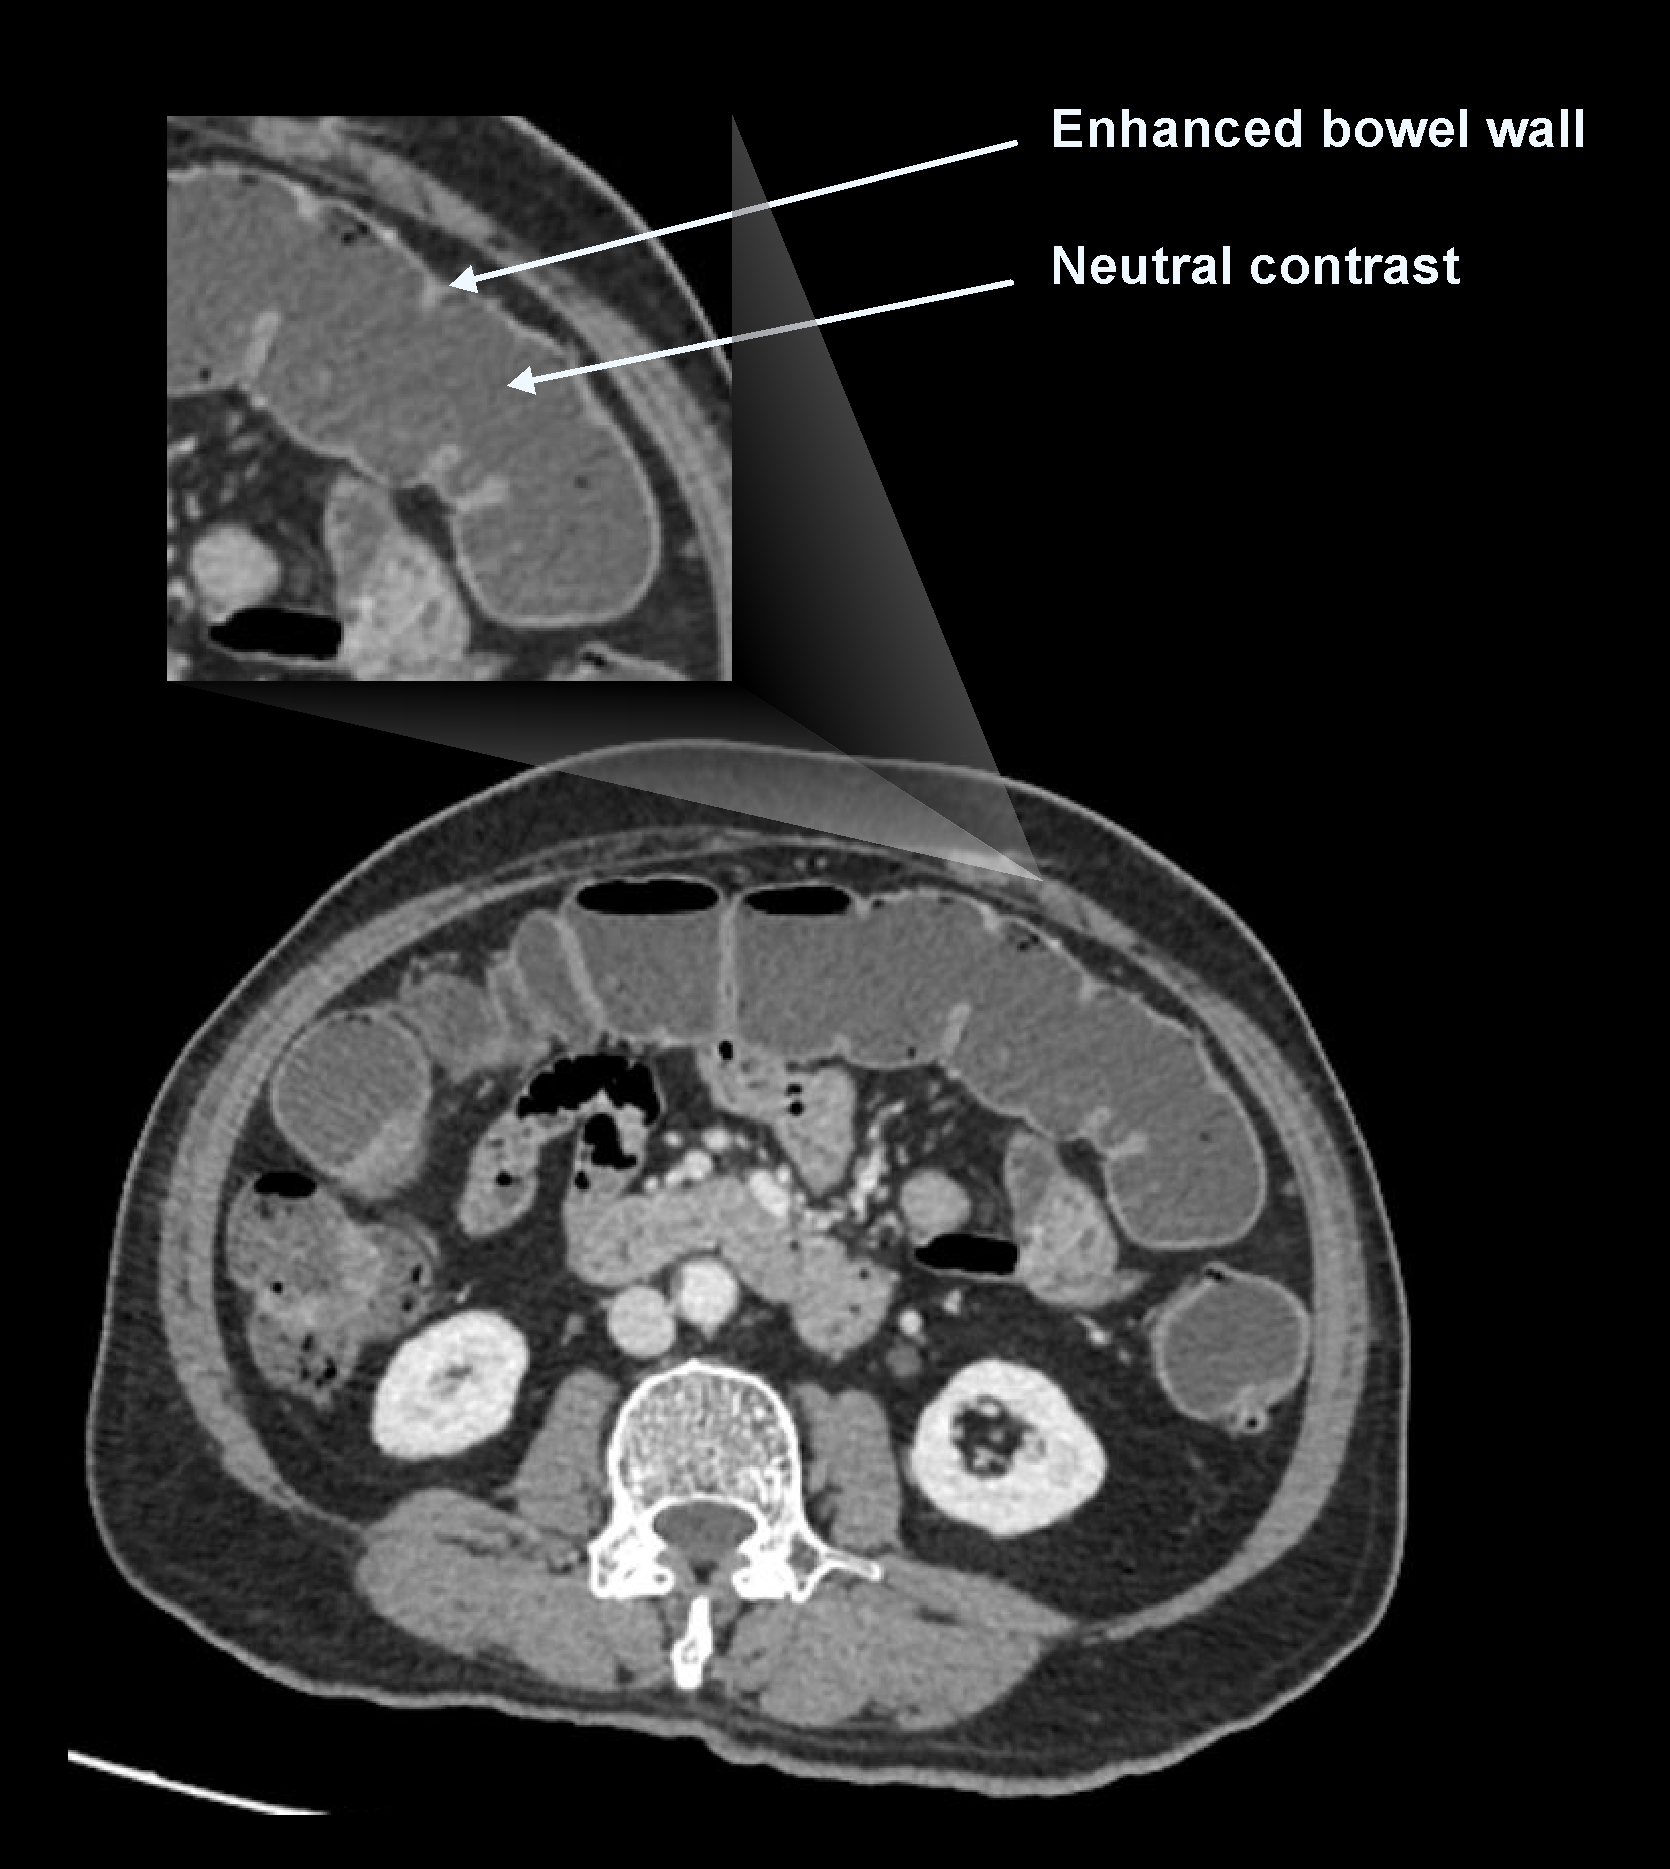

a. Neutral contrast media

Contrast media in this category have a density equal to water (nearly zero Hounsfield unit (HU) value). Water and mannitol can be used as neutral contrast media. Neutral contrast distends bowel, and their neutral appearance compared to bowel wall helps to differentiate bowel enhancement patterns and masses. However, they may obscure the visualization of extraluminal pathologies such as fluid collections, abscesses, masses, fistulas and perforations.